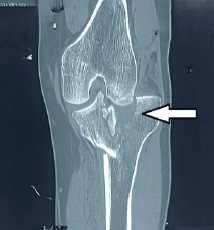

Ilizarov-Assisted Reduction of Femoral Condyle Locked in Tibial Fracture: A Case Report

Anteshwar Birajdar , Sushant Kumar , Setu Kaneria , Archit Gupta , Omkar Shinde , Sagar Gurnani

………………………………p.86-91